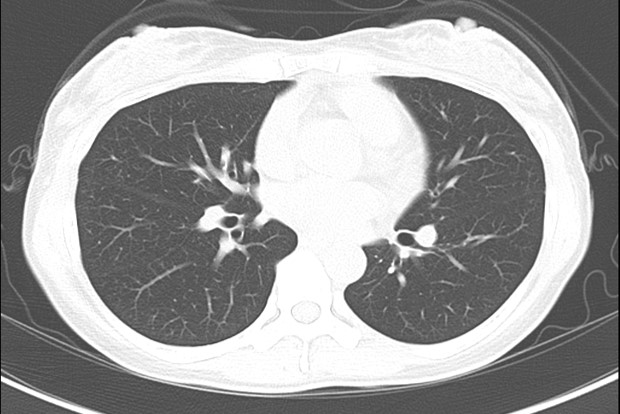

両肺野のすりガラス影の増悪

初診時

第5病日